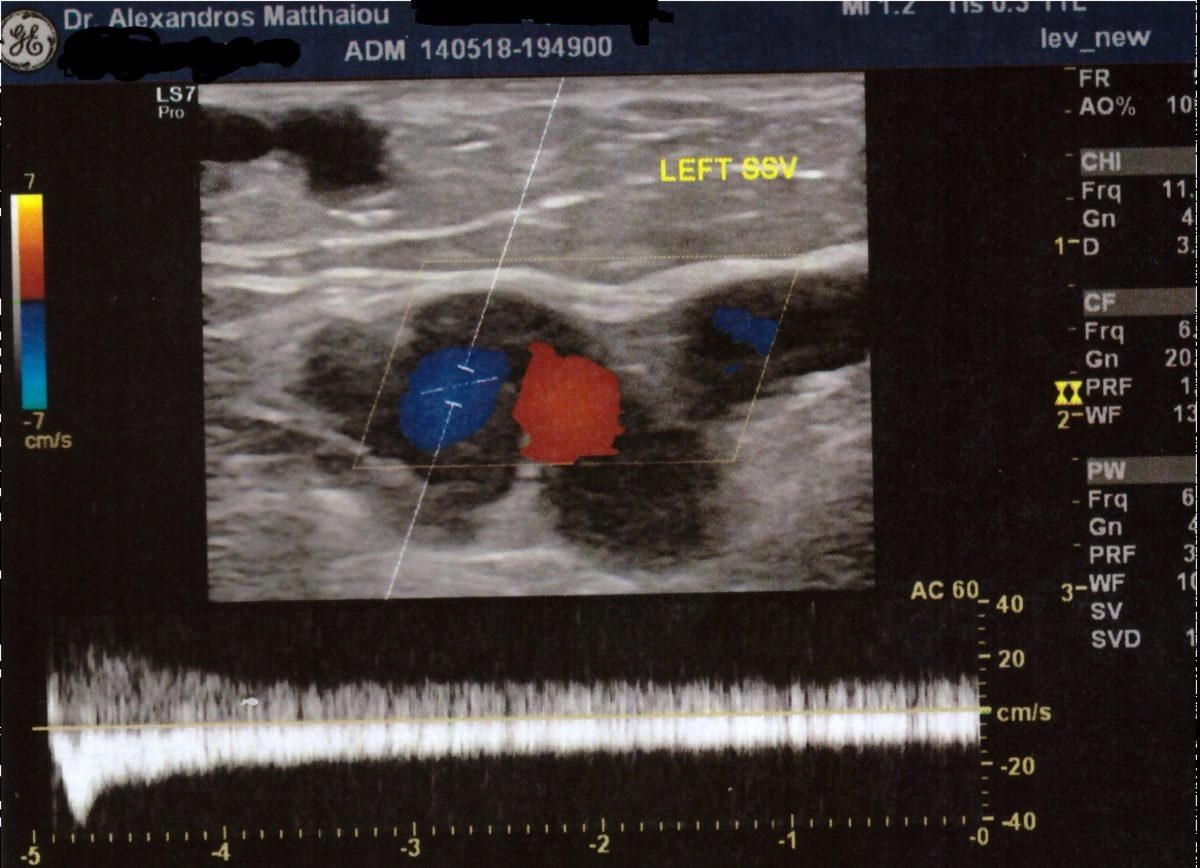

Όπως εξηγεί, η εξέταση με το έγχρωμο Duplex (Triplex), είναι μία εξέταση με υπέρηχους, η οποία είναι τελείως ανώδυνη και απόλυτα ανεκτή για τον ασθενή, αποκαλύπτοντας τόσο το εν τω βάθει όσο και το επιπολής φλεβικό «δέντρο», με ιδιαίτερη λεπτομέρεια, απεικονίζοντας την παρουσία της ροής του αίματος στις φλέβες, αλλά και το σημαντικότερο, την κατεύθυνση αυτής της ροής, προκειμένου να διαγνωσθεί τυχόν παλινδρόμηση.

«Ο απεικονιστικός έλεγχος με υπερήχους σε ασθενείς με κιρσούς είναι απαραίτητος καθώς αποτελεί το κλειδί για την σωστή διάγνωση των κιρσών και καθοδηγεί τον αγγειοχειρουργό στον σχεδιασμό της σωστής θεραπείας που θα προσφέρει άμεση ανακούφιση και άριστο λειτουργικό και αισθητικό αποτέλεσμα που διαρκεί», υπογραμμίζει ο κ. Ματθαίου και συνεχίζει: «Χρειάζεται όμως ο ιατρός να έχει εκπαιδευθεί στη χρήση των υπερήχων και παράλληλα να διαθέτει σημαντική εμπειρία».